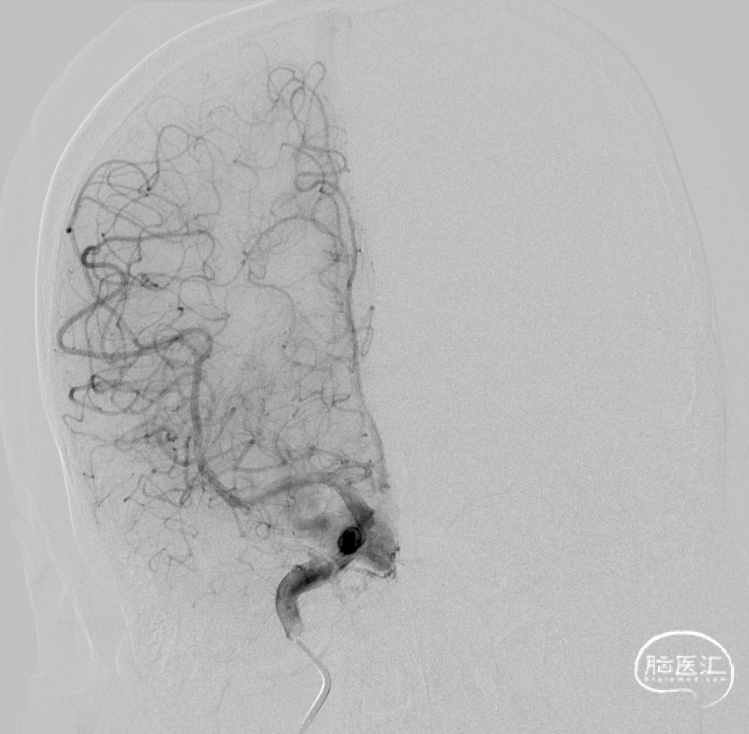

一期治疗

二期治疗